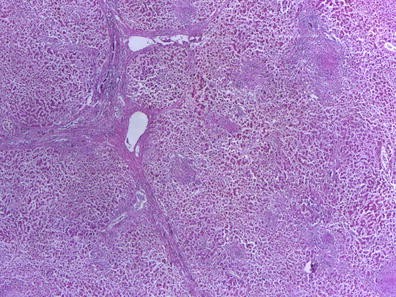

Method: The Betti numbers, which are consisting of two numbers (b1 and b0), can express the degree of the connection of the figure. When the number of contact points between individual components increases, irrespective of their shape, b1 and a ratio b1/b0 significantly change. We hypothesize these numbers can be used as indices to represent the cellular “accumulation” which is one of the characteristics of tumor tissue.

Results: Hematoxylin and eosin stained mucosal biopsy sections of colonic tumors are used as test samples. We compare the values, b1 and b1/b0, of colonic tumor tissues with those of normal tissues. As the values of b1 and b1/b0, we put color stones on unit area. The area of abnormal, it can be seen that the stone is placed

Conclusion: The results obtained in the present study clearly indicate that the difference in the Betti numbers can differentiate tumor tissues from their normal counterparts.

Numerical Results:

figure a